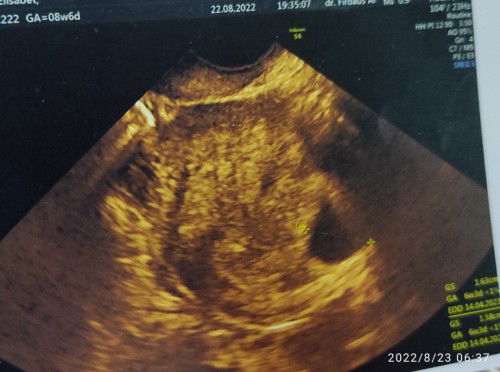

Blighted ovum (BO) Hamil kosong

Haid terakhir 25 juni 2022 Tgl 30juli usg 2D hasilnya masih penebalan rahim Tgl 23 agustus usg krn ada flek coklat usg 3D hanya keliahatan kantung saja, untuk meyakinkan dokter menyarankan Transvaginal Di nyatakan BO dokter menyarankan untuk kuret Dokter blg harusnya janin sudah terlihat diumur 8week, dan ini hanya kelihatan kantung janin saja Penyebab hamil BO krn kualitas sel telur atw sperma yg kurang baik Ini kehamilan anak ke 2 Dengan jarak 10thn dr anak pertama pagi ini flek kembali Mohon doanya Apa ada yang sama dengan saya?